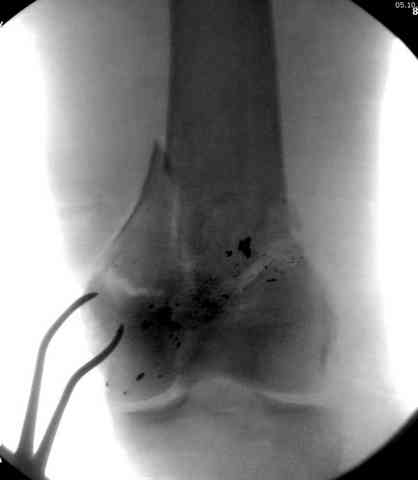

Пуля от ПМ - очевидно, что ранение было т.н. низкоэнегетическим, что подтверждается в том числе спокойным состоянием мягких тканей в этом, уже отсроченном периоде.

Однозначно, огнестрельные переломы стоит стабилизировать АНФ в максимально ранние сроки после получения ранения. Так же при ПХО или повторной ХО требуется фасциотомия. Эти две манипуляции приводят к улучшению паравульнарного кровотока и уменьшают вероятность развития вторичных осложнений. Дождавшись закрытия ран и при полной уверенности в отсутствии гнойных осложнений можно поднимать вопрос о конверсии наружного остеосинтеза на внутренний. Судя по снимку, пуля пистолетная, перелом не носит многооскольчатый характер, что дает основание полагать, что невысокая энергия ранения подразумевает невысокую вероятность вторичных осложнений и возможность внутреннего остеосинтеза. Конечно, БИОС в а\б муфте предпочтительнее ввиду щадящего отношения к кровообращению в заинтересованной области, но лучшая методика та, которой хорошо владеет хирург.

Характерным признаком травмы с низкой кинетической энергией является отсутствие "мультифрагментации и кавитации", и поэтому в данном случае лечение можно проводить любым доступным методом.

Здесь представлены несколько случаев лечения огнестрельного перелома

2 внутрисуставной перелом дистального бедра с удалением пули